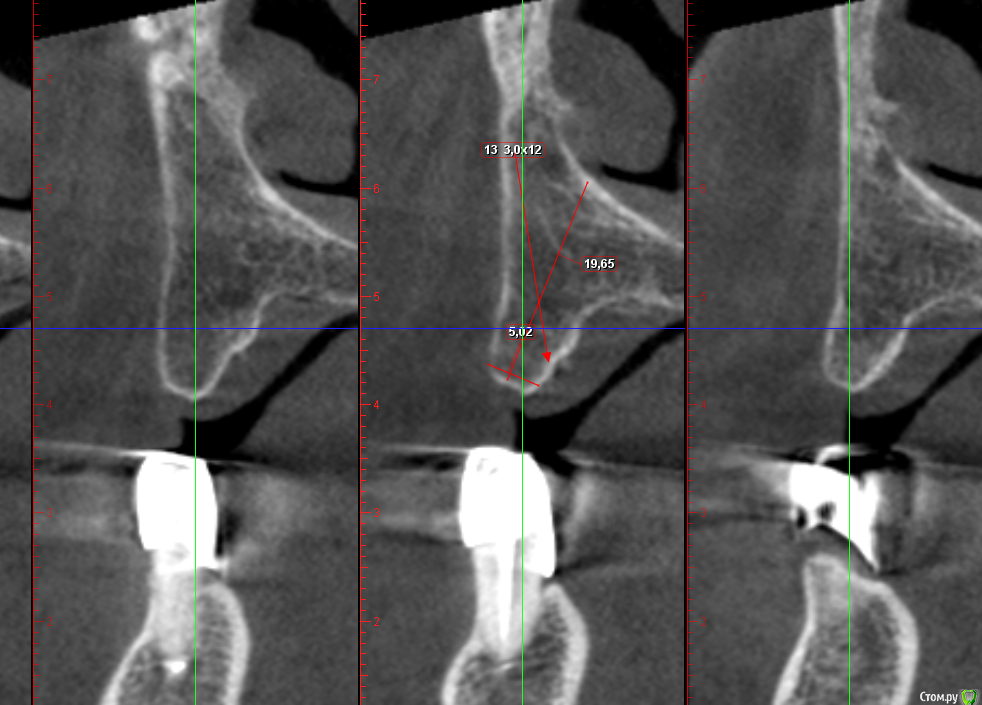

Sergiosse Опубликовано 4 марта, 2016 Поделиться Опубликовано 4 марта, 2016 Женщина 67 лет.полная адентия в\ч.Планируется установка 2-х Остем мини 3,0х12мм. с лабильными болл аттачменами. Ширина гребня 5мм.Есть сомнения выдержит ли кость нагрузку на трехмилиметровых импл.Альтернатива- расщепление и имплант 4.2мм. Заранее спасибо. Ссылка на комментарий

Аслан Опубликовано 4 марта, 2016 Поделиться Опубликовано 4 марта, 2016 как вариант, просто установить чуть глубже и немного досыпать вестибулярно при такой оси постановки импланта, как показаны измерения. Ссылка на комментарий

Nazim_NV86 Опубликовано 4 марта, 2016 Поделиться Опубликовано 4 марта, 2016 (изменено) у Osstem нет 4.2 диаметра. Все с шагом 0,5. Не советую расщеплять. Направление, выбранное на кт неверное. Ставьте не по центру гребня, а параллельно вестибулярной кортикалке.Зачем мини 3,0, когда можно 3.5х13 утопить? поставьте с помощью экспандеров и сразу фдм диаметром 4 если торк выше 45. Изменено 4 марта, 2016 пользователем Nazim_NV86 Ссылка на комментарий

stommm Опубликовано 5 марта, 2016 Поделиться Опубликовано 5 марта, 2016 По поводу имплантации 3.5*10-12 с заглублением. Если биотип тонкий, утолщить. Попробуйте нарисовать в ромексисе цилиндр 3.8*12, нагляднее будет. По поводу протезирования, один раз видел 2 шарика на вч. Мучались и врачи, и пациентка. После этого только балки, ну либо пспп. Ссылка на комментарий

Борис80 Опубликовано 8 марта, 2016 Поделиться Опубликовано 8 марта, 2016 Я бы рассматривал 3.5 и поглубже 1 Ссылка на комментарий